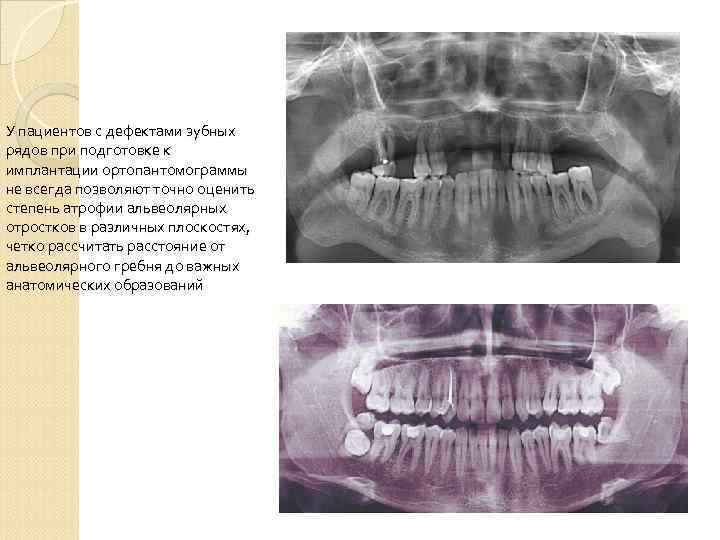

У пациентов с дефектами зубных рядов при подготовке к имплантации ортопантомограммы не всегда позволяют точно оценить степень атрофии альвеолярных отростков в различных плоскостях, четко рассчитать расстояние от альвеолярного гребня до важных анатомических образований

У пациентов с дефектами зубных рядов при подготовке к имплантации ортопантомограммы не всегда позволяют точно оценить степень атрофии альвеолярных отростков в различных плоскостях, четко рассчитать расстояние от альвеолярного гребня до важных анатомических образований